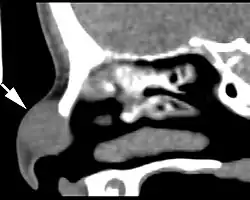

There is a subcutaneous nodule identified just below the nasal bridge in this computed tomography image of a nasal glial heterotopia.

Imaging studies are performed before surgery or biopsy to preclude an intracranial connection. Images usually show a sharply circumscribed but expansile mass. It may be difficult to exclude the intracranial connection if the defect is small whether employing computed tomography or magnetic resonance.[2]